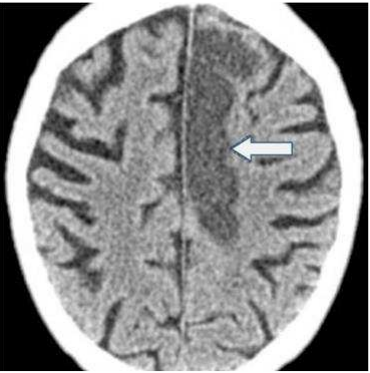

32.下圖箭號所指的診斷為何? (A)梗塞(infarction) (B)出血(hemorrhage) (C)腫瘤(tumor) (D)骨折(fracture)